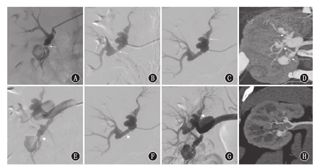

所有患儿均为FMD引起的单侧肾脏分支病变,无其他脏器动脉受累。涉及二级分支6例,涉及三级分支2例;累及2条及以上分支动脉4例,累及1条分支动脉4例;伴有囊性扩张或动脉瘤5例,其中发生夹层动脉瘤伴局部肾梗死患者1例,伴动脉瘤且动脉瘤位于分支分叉处者1例;仅发生动脉狭窄3例。局灶性病变者5例,其中管样狭窄2例;多灶性病变(指呈"串珠样"改变或多处血管损害)3例。相关病变类型分布见表1,图1、图2。

Selectively renal artery angiographies and computed tomography angiography before and after operation

注:A、B、C:显示此患儿3支肾动脉发生严重狭窄伴分支动脉瘤(箭头示狭窄部位);D:术前CT血管造影显示肾脏局部灌注缺血(白线以上区域低灌注);E、F、G:显示术后血管通畅(三角形示狭窄解除);H:术后1年CTA显示血管通畅和肾灌注良好,动脉瘤未见明显变化

A,B,C:the children with 3 renal artery severe stenosis with branch aneurysms (arrows showed stenosis);D:preoperative computed tomography angiography showed renal perfusion ischemia,hypoperfusion in the upper pole of the right kidney (above white line);E,F,G:vascular patency after operation (triangular showed stenosis release);H:1 year after operation,computed tomography angiography showed vascular patency and maintained renal perfusion,no obvious changes in aneurysms

在FMD累及的肾动脉分支病变中,1例出现多发的二级或三级分支动脉瘤伴分支严重狭窄,动脉瘤位于分支动脉分叉处,无明显瘤颈,且动脉瘤最大直径10.6 mm×12.6 mm(图3),考虑到患儿的年龄较小(12岁)及较高的介入手术风险,暂不处理分支动脉瘤,仅给予狭窄处球囊扩张术。1例出现动脉瘤伴夹层样改变,分支动脉涉及的肾脏组织发生肾梗死,患儿血压可以通过药物得以良好控制,因此未实施手术治疗(图3)。所有行介入治疗的7例患儿手术成功率为100%,无明显动脉夹层、破裂、栓塞等手术并发症(图1、图2)。术后1周患儿血压明显改善,肾功能未见异常,肾素活性水平下降,GFR恢复。

在1年的随访中,2例患儿病变部位出现再狭窄(再狭窄率为28.6%),其中1例在术后第4个月出现血压突然增高,增加药物控制血压不佳,再次行DSA发现病变部位再狭窄,再次行球囊扩张;另1例患儿在术后6个月随访中CTA显示病变部位明显再狭窄(80%),予再次腔内治疗。所有患儿1年的随访中3例血压改善,4例高血压治愈(治愈率57%)。1年后复查CTA显示狭窄部位血流通畅,无明显狭窄。1例患儿伴多个肾内分支动脉瘤,尽管未予处理,但1年后随访动脉瘤保持稳定(术后随访最大动脉瘤直径10.6 mm×9.4 mm,见图1)。